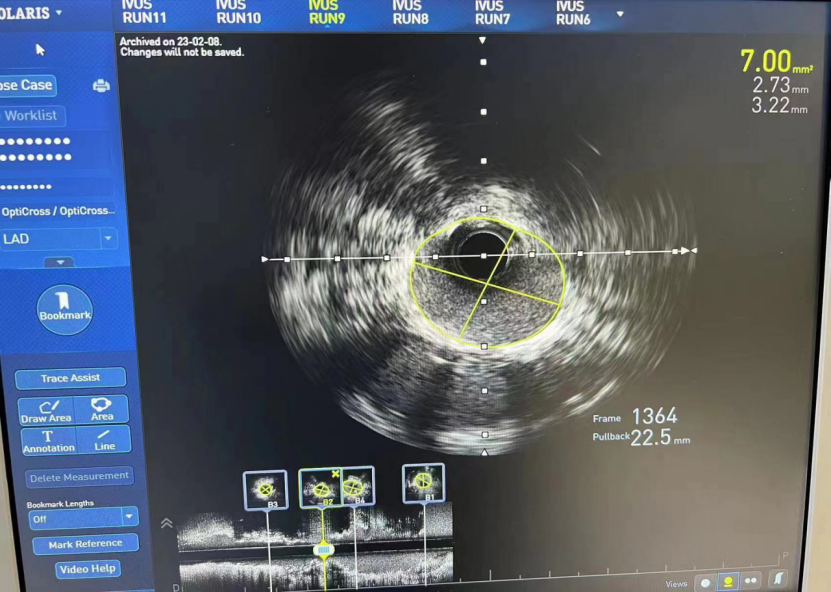

LM

MSA 最小支架腔内面积 12.94mm²

LAD

MSA 最小支架腔内面积 7.0mm²